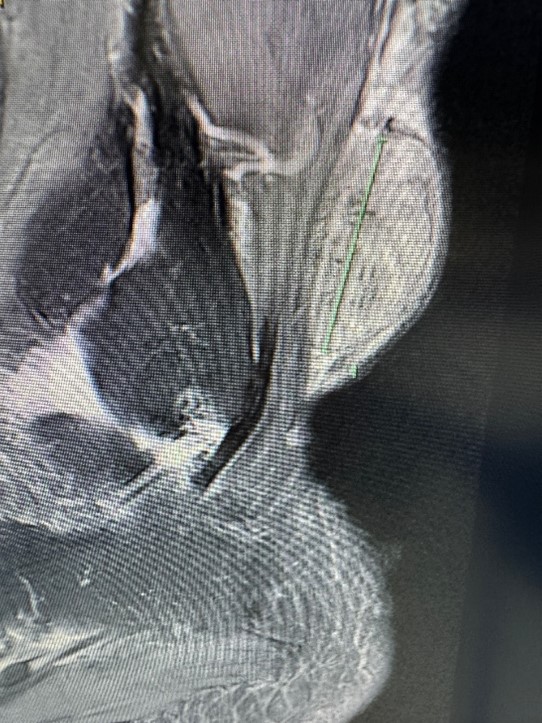

67 year old man with a large slowly growing tumour on the back of his ankle. MRI showed central necrosis and the size was of concern. The tumour turned out to be a benign angioleiomyoma